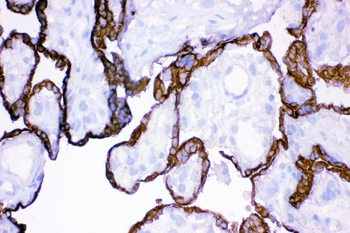

10 μg, 100 μg - Anti-Annexin IV/ANXA4 Antibody [orb18546]

FC, IHC, WB

Human, Mouse, Rat

Rabbit

Polyclonal

Unconjugated

10 μg, 100 μg - Anti-HSPB8/Hsp22 Antibody [orb18992]